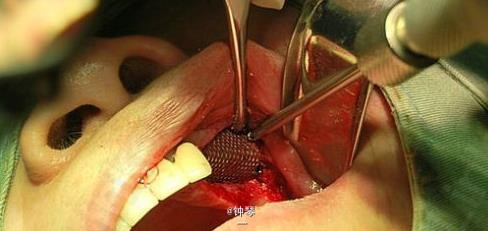

刀刃状牙槽嵴种植+钛网应用

左上3、4、6种植